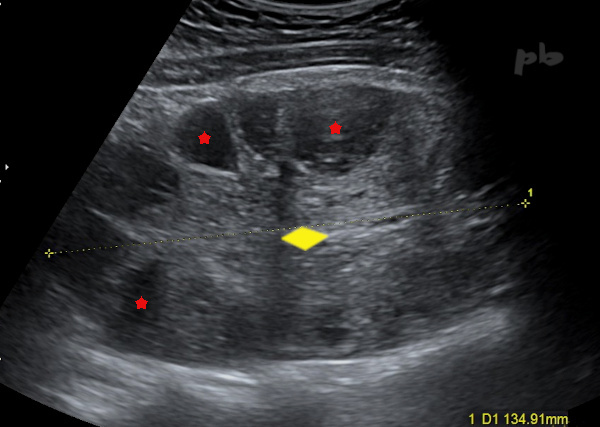

5 – Torsion – Abdominal Ultrasound

Pain occurring in the context of ovarian hyperstimulation. Very large ovary (between the crosses: 135 mm) with multiple peripherally located follicles (★). The ovarian stroma (♦) is abundant and hyperechoic. No vascular flow was detected on color Doppler. In the context of hyperstimulation, a large ovary is not surprising, but the stroma is usually sparse and vascularization is intense: the appearance here is therefore highly suggestive of torsion. Adnexal torsion is a classic complication of ovarian hyperstimulation.